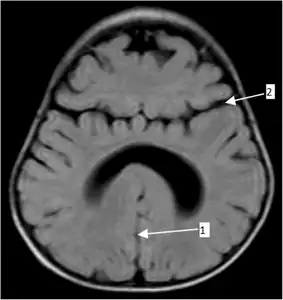

Semilobar holoprosencephaly-MRI shows incompletely interhemispheric fissure arrow 1 and partial fusion of frontal lobe arrow 2

- Semilobar holoprosencephaly, in which the brain's hemispheres have somewhat divided, is an intermediate form of the disease.